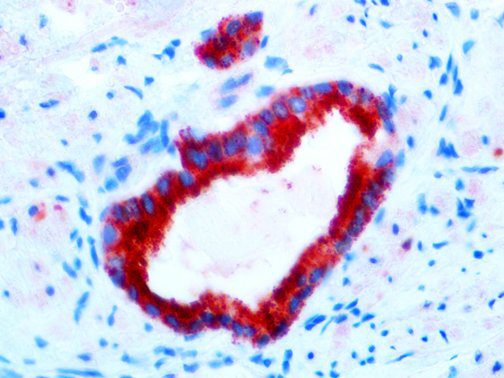

This activation induces inflammatory monocytes to highly express IL-6, starting a localized and then systemic cascade effect that results in hyperproduction of IL-6, which accelerates the inflammatory process. Because IL-6 also increases vascular permeability, excessive levels cause blood vessels to become very leaky. This, along with clotting factors released from vascular endothelial cells, stimulates the coagulation cascade, resulting in microthrombosis (tiny clots), which leads to ischemia and tissue death of the kidney, intestines, heart, liver, brain and extremities.